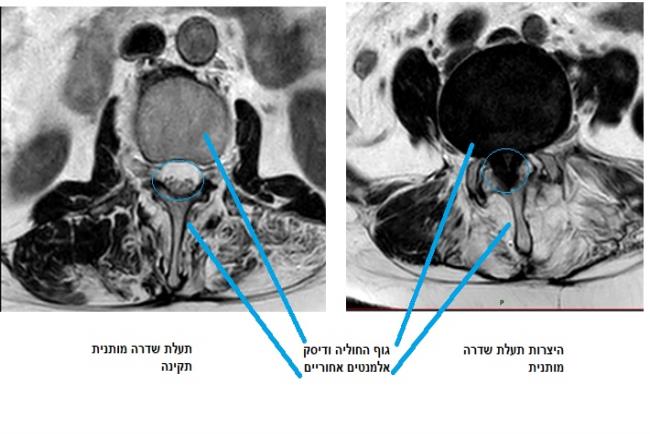

כאמור, היצרות תעלת השדרה נגרמת עקב פתולוגיות דומות. כתוצאה מהן קוטר התעלה קטן ואינו מספק את צורכי חוט השדרה הנמצא בתוכה. ההיצרות יכולה להיות מולדת או להתפתח בשל פתולוגיות מסוימות. הסיבה השכיחה ביותר להתפתחותה היא ניוונית(דגנרטיבית). תעלת השדרה שלנו מורכבת מגופי החוליות והדיסקים בחלקה הקדמי ובחלקים הצדדיים והאחוריים קשתות גרמיות, מפרקים וליגמנטים (רצועות). היצרות תעלה ניוונית נגרמת מהיפרתרופיה (גדילה לא תואמת) של כל אחד מהאלמנטים שתוארו לעיל.אילו תסמינים יעלו חשד להיצרות של עמוד השדרה?

הניתוח מתבצע דרך חתך אחורי בגב, לעיתים באופן פתוח או בגישה זעיר פולשנית. במהלך הפעולה, מסיר הרופא המנתח את האלמנטים שלוחצים על תעלת עמוד השדרה. לעיתים לאחר שחרור הלחץ יתבצע קיבוע כדי לשמור על יציבות עמוד השדרה.